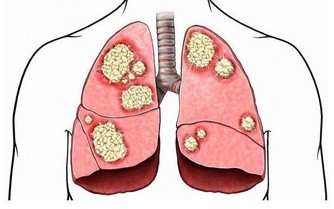

9、敲打雲門穴(換肩) 這個動作刺激到的是中府、雲門等肺經穴位,針對肺系疾病、氣管、支氣管疾病均有治療作用。此外,中府穴還有診斷治療肺癌的作用。 http://www.102like.com/manage/0/product/13867/13867_9.gif